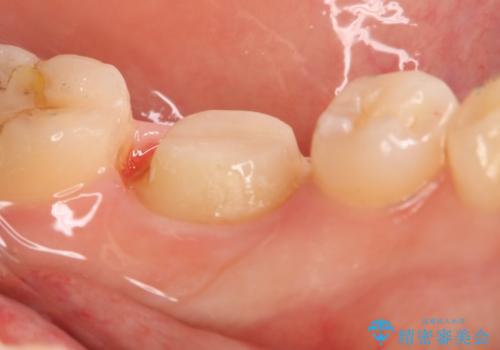

- 左下大臼歯の歯肉に腫れと痛みが繰り返し起こっているので治療を希望し来院された患者様です。

既に治療されている歯でしたが根尖部に病巣が確認出来たので、精密根管治療とクラウンの再治療が必要と判断されました。